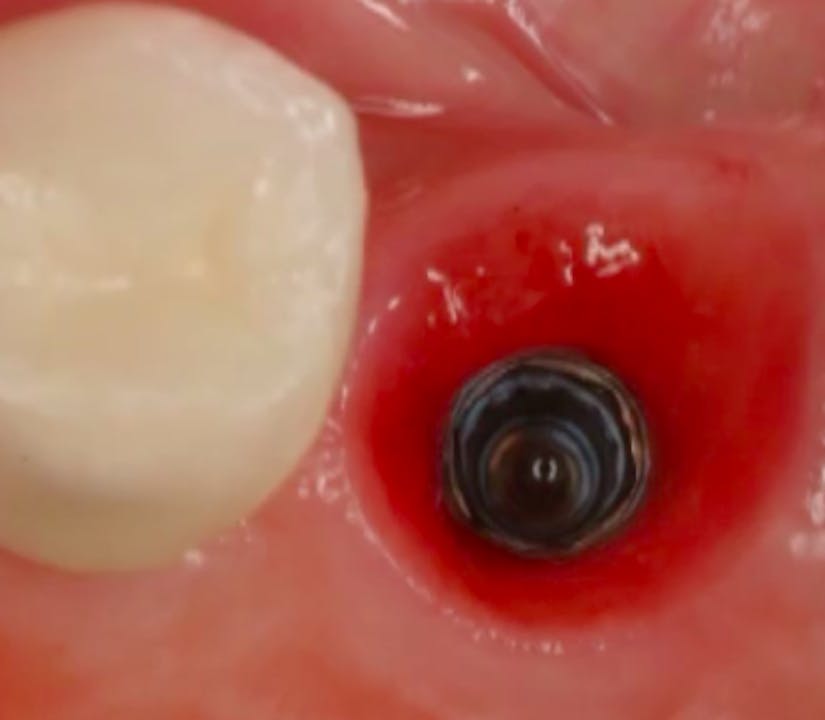

Immediate Implant Placement in the Esthetic Zone gIDE Dental Institute Gide Dental Reviews • 550+ clinical videos on web and app • new dental videos added. Premiere provider of online dental education. 31,762 likes · 74 talking about this · 887 were. Read 26 customer reviews of gide dental center, one of the best. Find reviews, ratings, directions, business hours, and book appointments online. Gide dental | 280 followers on linkedin. Gide dental. Gide Dental Reviews.

CLINICAL VIDEO Immediate Tooth Replacement with Simultaneous Socket and Gide Dental Reviews 31,762 likes · 74 talking about this · 887 were. Read 26 customer reviews of gide dental center, one of the best. Gide dental | 280 followers on linkedin. Clinical videos, expert interviews, live broadcasts over. • 550+ clinical videos on web and app • new dental videos added. Dive deep (at your own pace) in a comprehensive online master. Gide Dental Reviews.